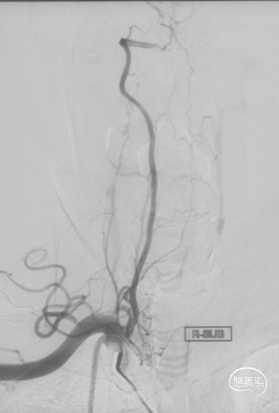

CTA和DSA

CTA和DSA所见:双侧颈内动脉闭塞,右侧椎动脉发出PICA后闭塞,左侧椎动脉V1-V2段闭塞。两条健壮的侧枝通过肌支吻合汇入左椎动脉V2段,构成了整个大脑大部分供血的主要来源。双侧颈外动脉亦有少量血流供应颅内。这样的颅内供血很容易发生失代偿,导致TIA甚至脑梗。